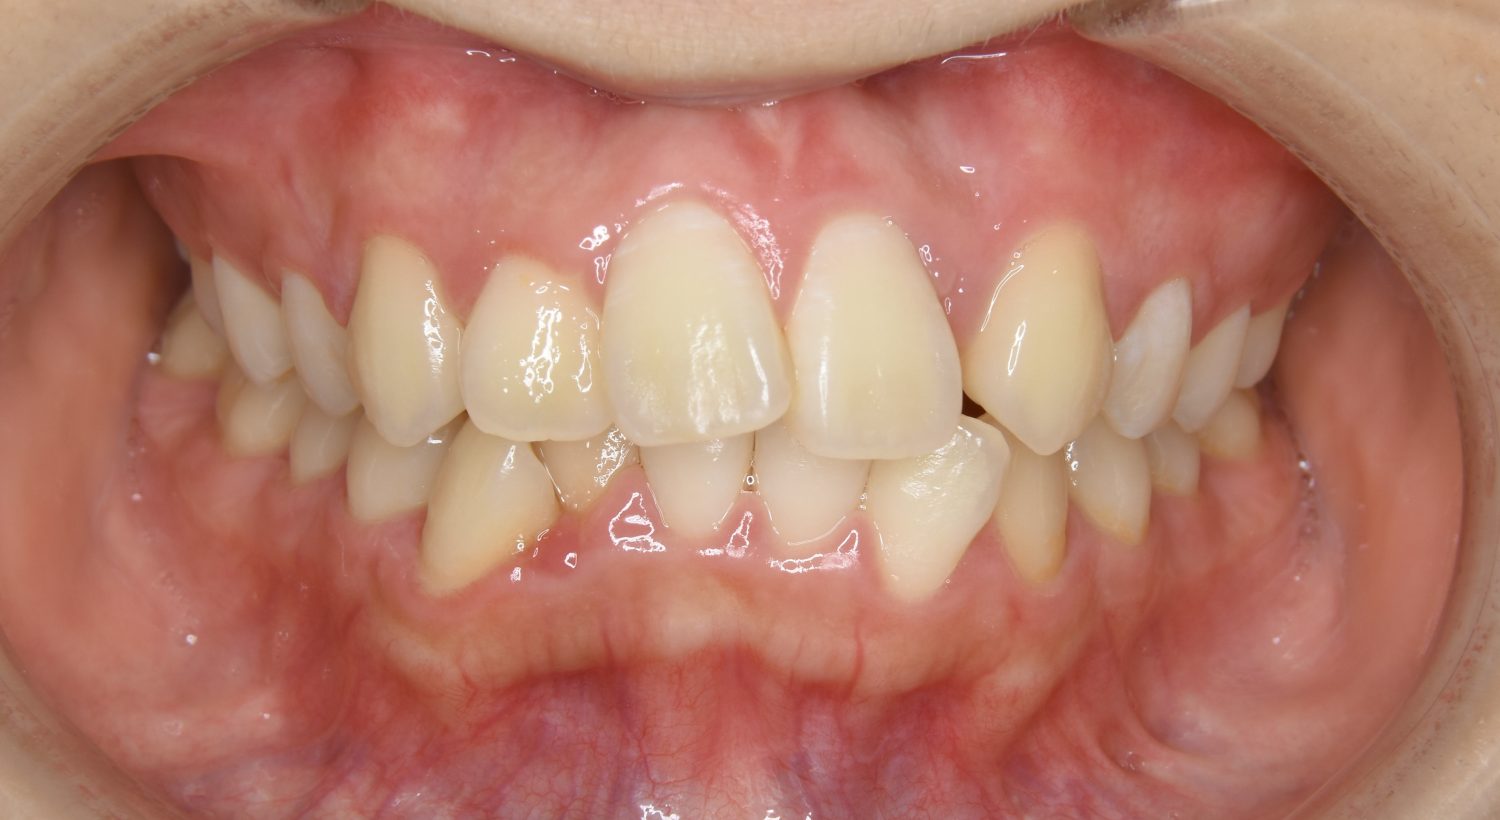

叢生の症例紹介②

Before

After

主訴

歯の凸凹を治したい。

治療内容

アライナー(インビザライン)にて非抜歯で治療を行いました。

上下前歯部に叢生(凸凹)が認められる状態でした。歯列の遠心移動を行うことで機能面および審美面が改善されました。